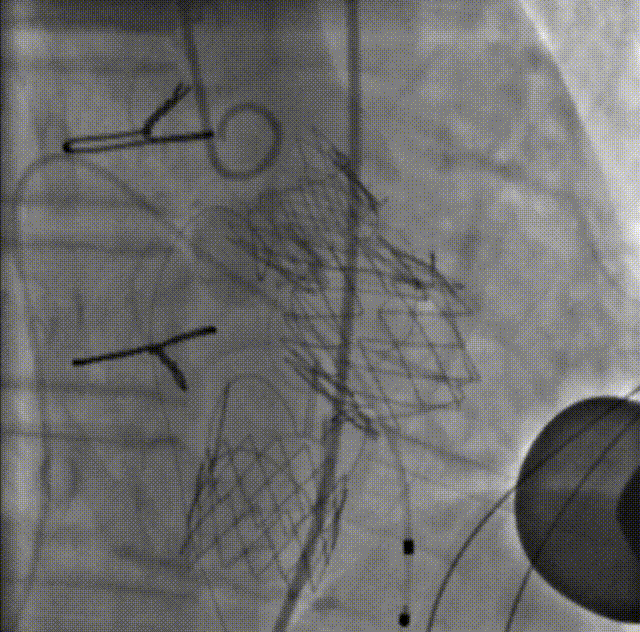

术前造影

瓣膜仓入位

瓣膜仓打开

锁丝释放

球囊后扩

二尖瓣入位

主瓣造影

左室造影